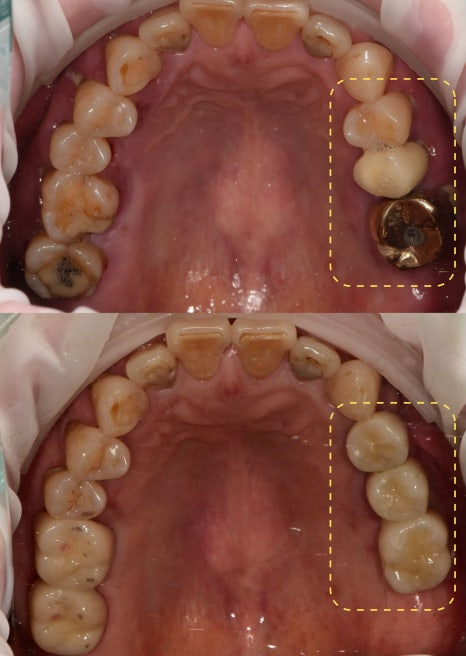

23.12.15 — 아래 임플란트 식립 / 24.09.04 — 치료 완료

위 회복 확인 후 아래를 순차적으로 진행했습니다. 빠르게 끝내는 것보다 각 단계마다 회복을 확인하며 진행하는 방식을 택했습니다. 총 치료기간은 약 1년 4개월이었습니다.

※ 전·후 사진은 동일인, 동일 장소, 동일 각도·조명 조건에서 촬영되었습니다.

23.04.25 (치료전)- 24.09.04 (치료후)